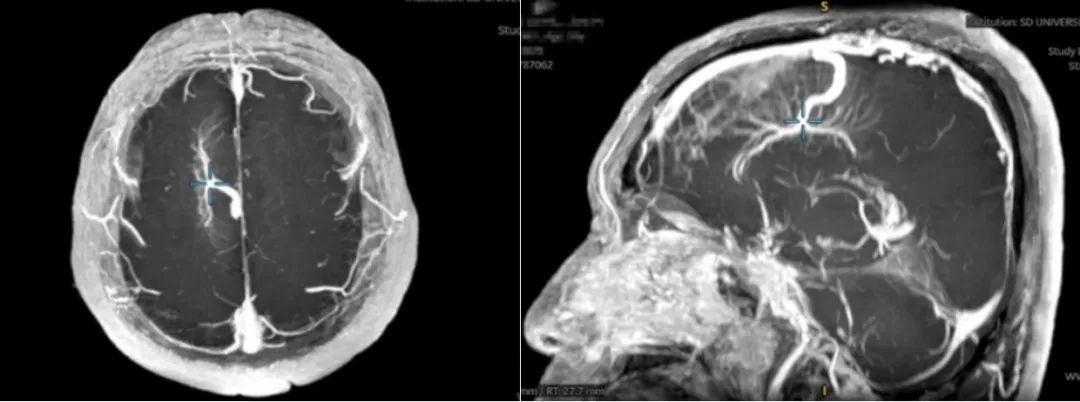

结构特征:异常扩张的静脉呈"水母头"状(中央粗大引流静脉+放射状小静脉)

MRI+SWI(磁敏感加权成像):清晰显示"水母头"特征